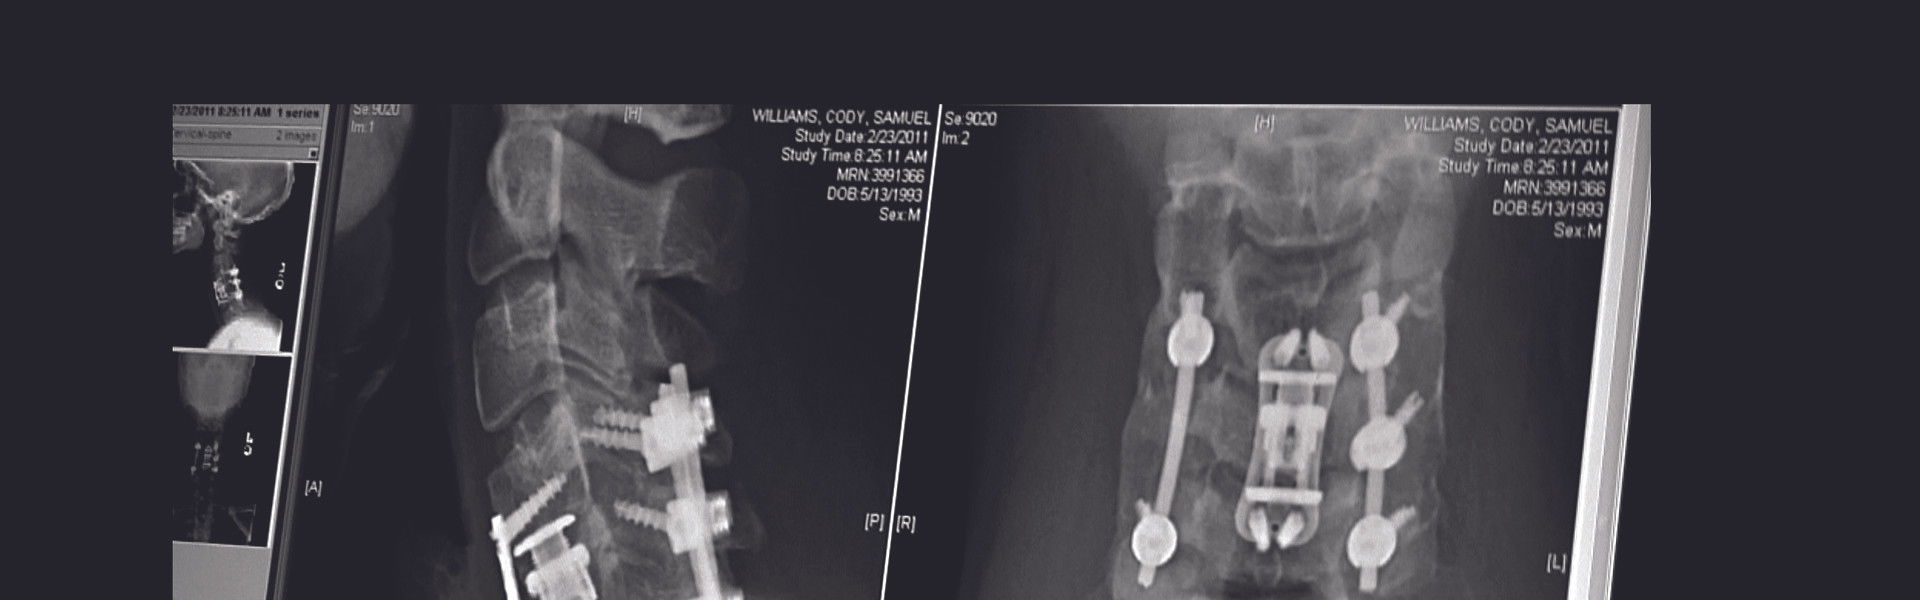

The compelling, heart-wrenching story of high school football star Chris Carnales, whose life changed when he became paralyzed after breaking his neck in a football game. Chris soon learned of others who suffered similar injuries and, with the help of his father, overcame tremendous pain to start an organization with one goal in mind: get immediate help to other victims and their families. He called it Gridiron Heroes.